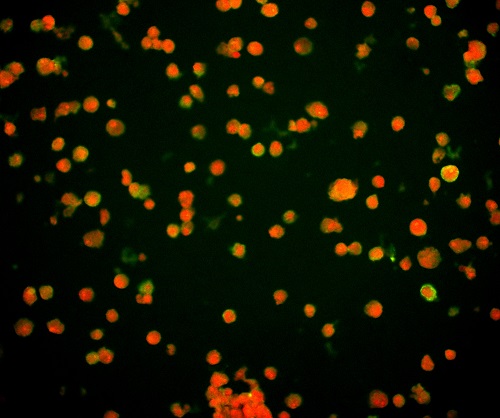

(1)通过观测对病毒进行特异性标记产生的荧光信号,从而实现对病毒位置数量的判断。病毒主要由核酸和蛋白质组成,常见的一种方法是利用荧光标记的特异核酸探针与病毒含有的靶DNA分子或RNA分子进行杂交,可通过在荧光显微镜下观察荧光信号,来确定与特异探针杂交后被染色的病毒的分布和数量,这种方式也称为原位荧光杂交技术(FISH)。

FISH做的病毒检测,红色为病毒外壳蛋白

(引自公开论文https://doi.org/10.1073/pnas.1820132117)